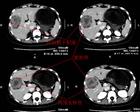

胰腺炎: 是胰腺因胰蛋白酶的自身消化作用而引起的疾病。胰腺有水肿、充血,或出血、坏死。临床上出现腹痛、腹胀、恶心、呕吐、发热等症状。化验血和尿中淀粉酶含量升高等。可分为急性及慢性二种。 胆道疾病。胆囊炎,胆石症。酗酒和暴饮暴食。十二指肠乳头部病变。十二指肠溃疡或炎症。流行性腮腺炎,病毒性肝炎,腹腔手术,腹部外伤,某些药物也可引起胰腺炎发作。